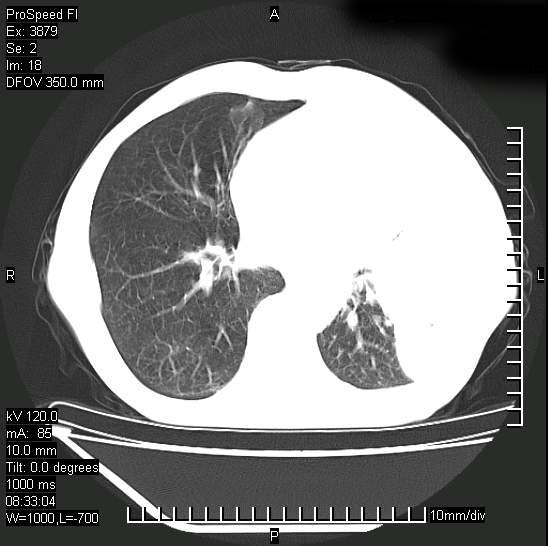

以下是引用37度在2008-6-6 11:20:00的发言:[br]1.包裹性积液,多考虑结核性;[br]2.穿刺术后改变。

以下是引用312nanyang在2008-6-6 15:12:00的发言:[br]基本支持楼主意见[br]疑问?左下肺支气管旁的软组织(16层)密度怎么解释?淋巴结还是斜裂胸膜增厚所致?能否增强进一步检查